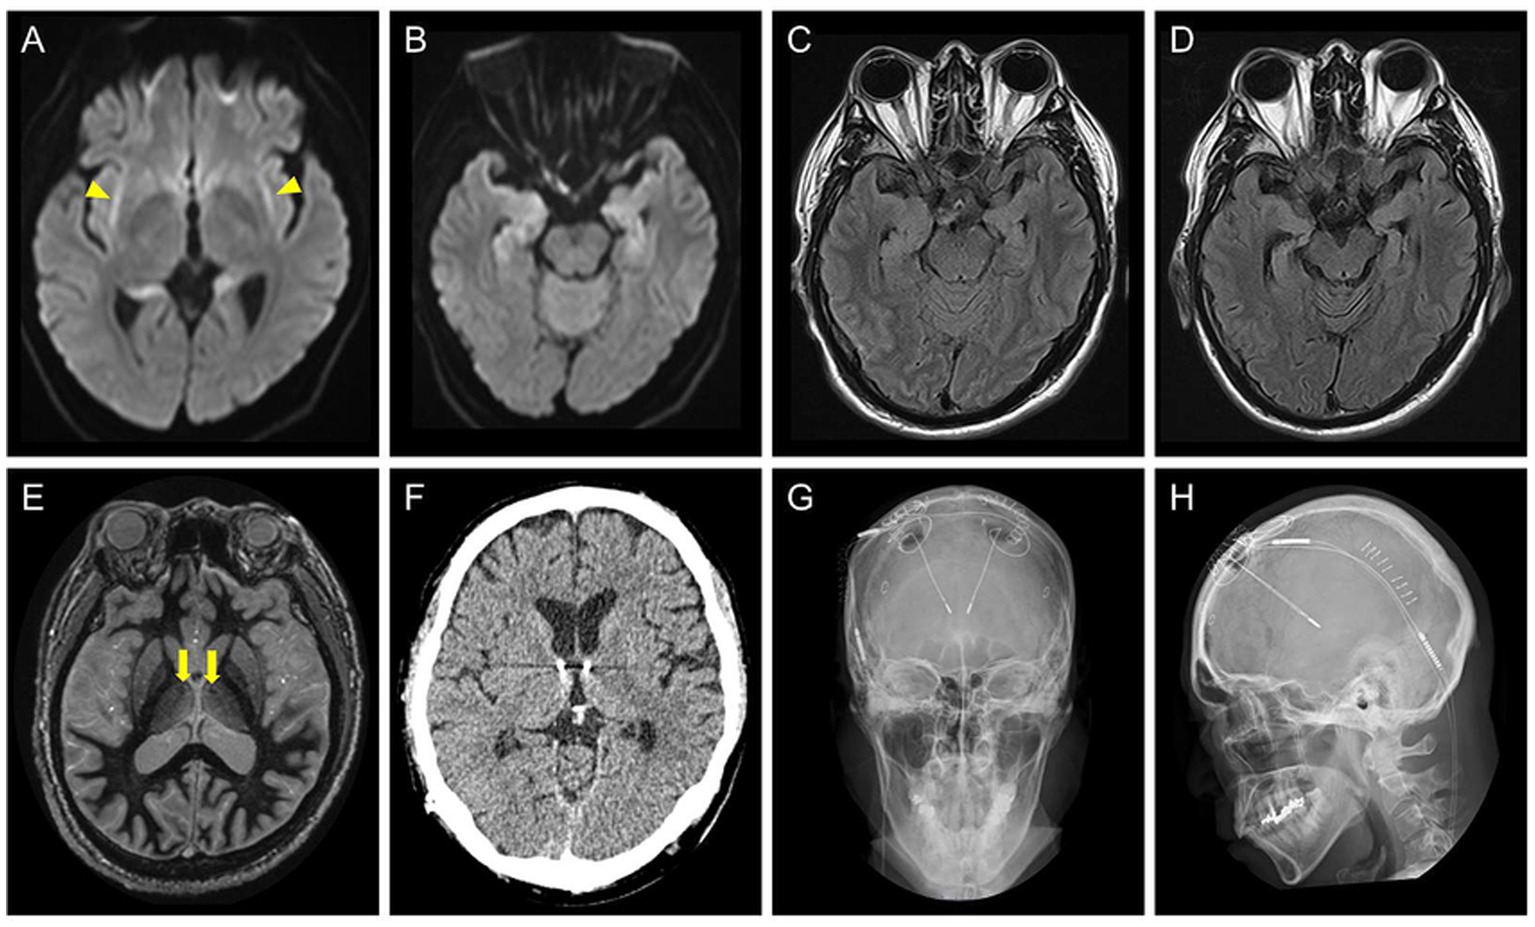

A 52-year-old right-handed man with DRE visited our hospital for comprehensive preoperative assessment of epilepsy. At the age of 45 years, he developed C-NORSE, which required intensive treatment, including intubation. Cerebrospinal fluid (CSF) analysis revealed 12 white blood cells/μL and normal protein and glucose levels. Magnetic resonance imaging (MRI) during the acute phase showed bilateral claustrum signs and mesial temporal abnormalities (Figures 1AC). An autoimmune mechanism was initially suspected and extensively examined at the laboratory of Josep Dalmau (Barcelona) through Kitasato University for potential autoantibodies against neuronal surface antigens, including NMDA, AMPA, GABA(A), GABA(B), mGluR1, and mGluR5 receptors, LGI1, Caspr2, DPPX, Neurexin3, and Iglon5, with established assay using in-house immunohistochemistry and cell-based assay; however, no neuronal surface autoantibodies were identified in CSF. The patient was finally diagnosed with C-NORSE and was treated with numerous anti-seizure medications (ASM), corticosteroids, and high-dose immunoglobulins; despite this, he ultimately developed DRE. No other relevant medical or family history was found. The patient was administered lacosamide 400 mg, perampanel 8 mg, levetiracetam 2,500 mg, lamotrigine 175 mg, valproic acid 600 mg, and prednisolone 25 mg.

Figure 1. (A–C) Brain axial MRI of the patient at the age of 45 years, during the acute phase of cryptogenic new-onset refractory status epilepticus. Diffusion-weighted images show bilateral claustrum signs (A, yellow arrowheads) and bilateral hippocampal abnormalities (B). A fluid attenuated inversion recovery (FLAIR) image shows high signal intensity areas in the hippocampi (C). (D) The axial FLAIR image at the age of 51 years showing progression of atrophy of the bilateral hippocampi. (E) A preoperative fast gray matter acquisition T1 inversion recovery sequence at the age of 52 years shows the intact mammillothalamic tract (yellow arrows). (F–H) Postoperative brain axial CT (F) and skull radiographic (G,H) images showing placement of the stimulation leads.

The seizure semiology comprised FAS with palpitations, chills, and nausea, followed by FIAS with oral automatism multiple times a day. Neurological examination findings were unremarkable except for cognitive dysfunction. Assessment using the Wechsler Adult Intelligence Scale-4th edition revealed low intelligence scores (Full Scale Intelligence Quotient 64, Verbal Comprehension Index 77, Perceptual Reasoning Index 69, Working Memory Index 71, Processing Speed Index 66, and General Ability Index, 70). MRI showed bilateral hippocampal atrophy, whereas the mammillothalamic tract was intact (Figures 1D,E). vEEG showed bilateral independent spikes and electrographic seizures (ESz) arising from the fronto-temporal areas. Based on the diagnosis of DRE with multiple seizure foci in the bilateral mesial temporal lobes, the patient underwent ANT-DBS (Figures 1FH). Stimulation was started on the 7th postoperative day with the following parameters: 1 mA (gradually increased to 1.5 mA and then 1.8 mA every 6 weeks), 145 pulses/s, 90 μs, 1 min on, and 5 min off.